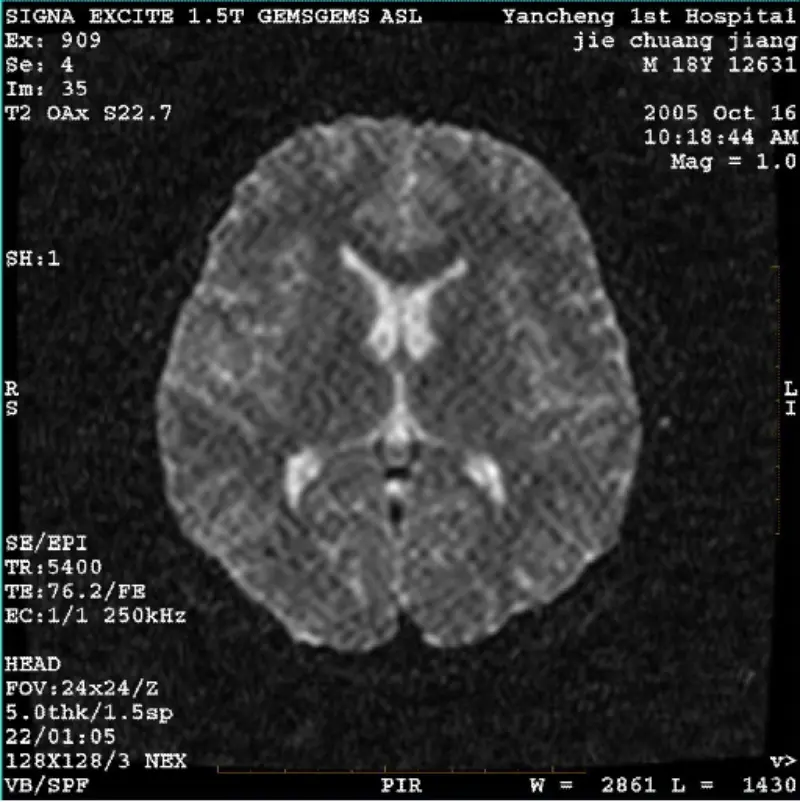

Devamını okuSİSTEM: 1.5T Signa Twin Excite II (Yazılım Sürümü 11.0M4) SORUN/BELİRTİ DWI (Yakınlaştırma modu ve tam mod) ve fiesta (yakınlaştırma modu ve tam mod) görüntüsü Gövde bobini veya başlığı kullanıldığında, ağ şeklinde veya fitilli kadife artefaktın görünür olması bobin, diğer rutin görüntü norma......